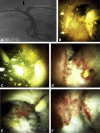

Percutaneous antegrade digital cholangioscopy in the management of biliary disorders